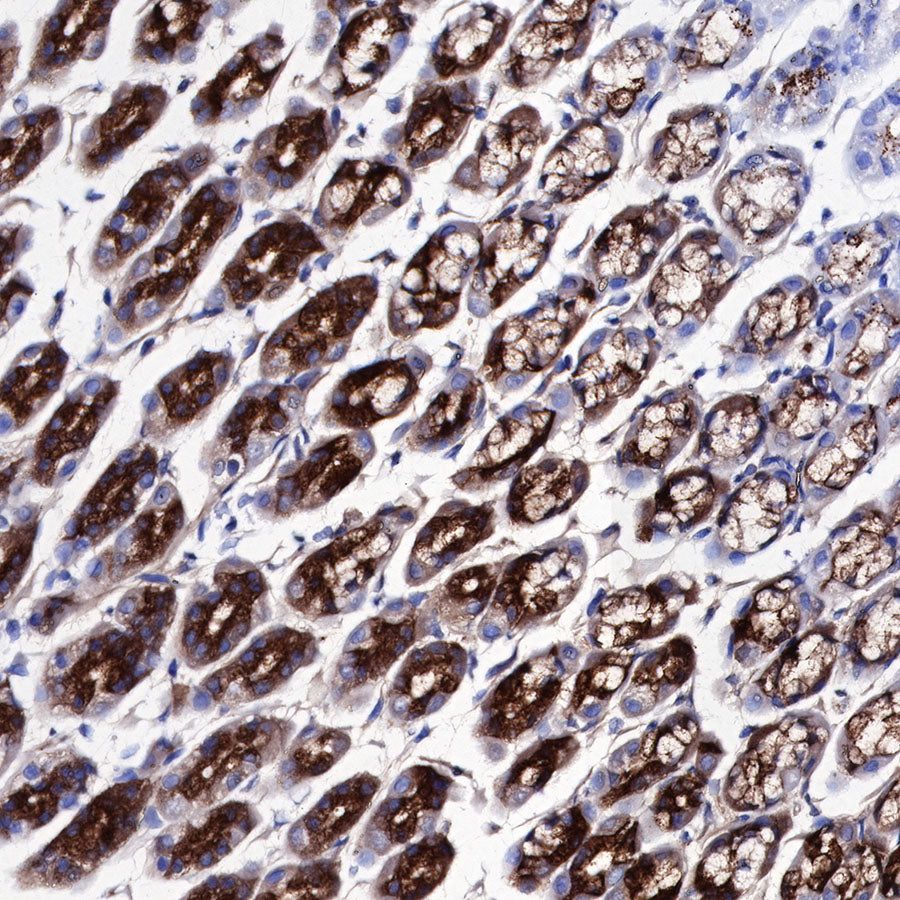

Immunohistochemistry

IHC shows positive staining in paraffin-embedded mouse stomach. Anti-PG II/PGC antibody was used at 1/1000 dilution, followed by a HRP Polymer for Mouse & Rabbit IgG (ready to use). Counterstained with hematoxylin. Heat mediated antigen retrieval with Tris/EDTA buffer pH9.0 was performed before commencing with IHC staining protocol.